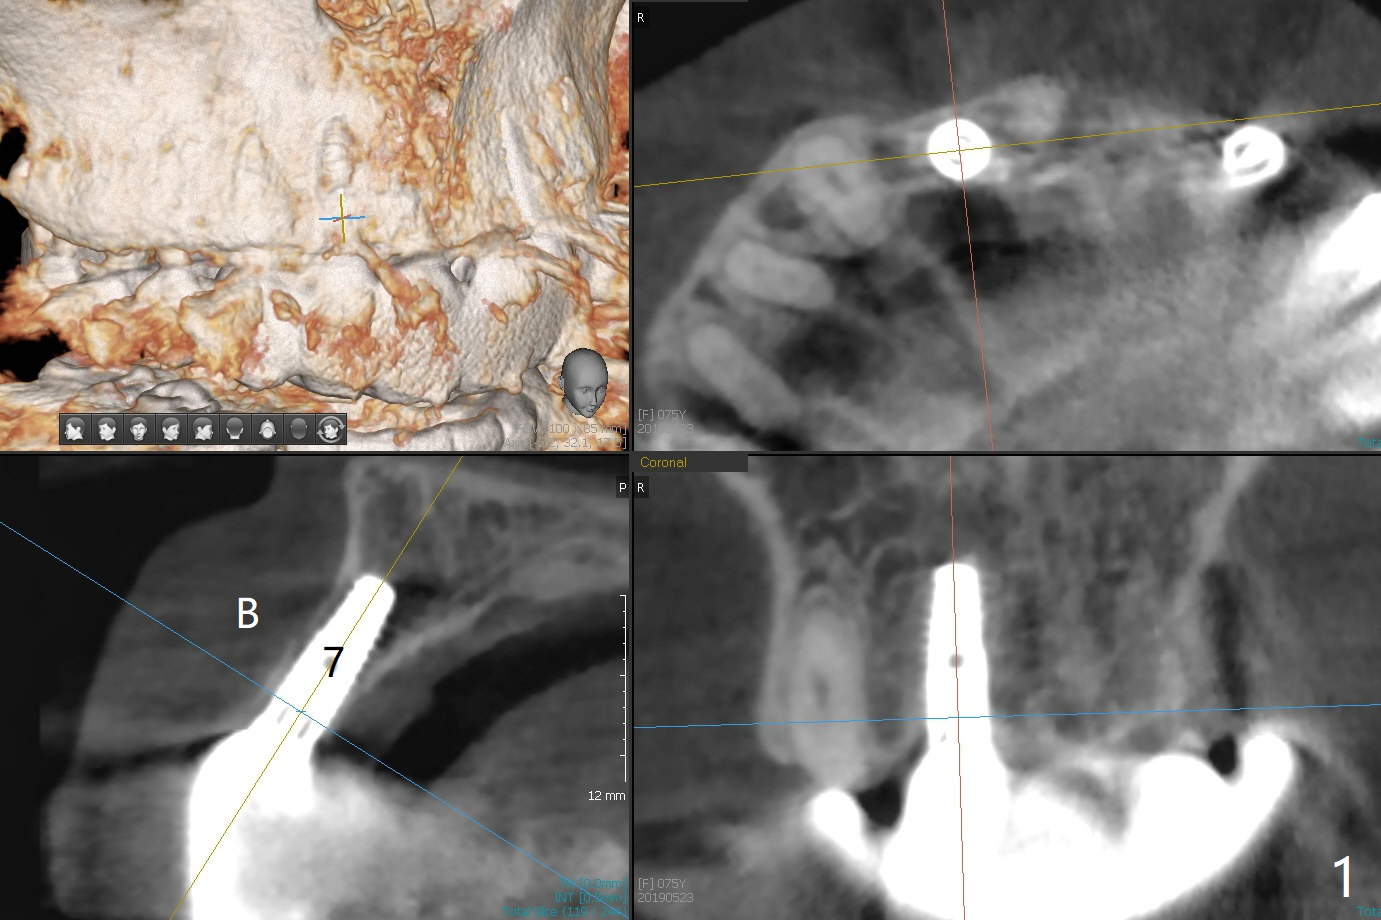

When the 75-year-old woman presents to clinic with #25 mobility, she is also concerned about gingival hemorrhage. It appears that the buccal plate is lost at #10 and 30 (Fig.2,3), as compared to #7, 19, 20 (Fig.1,4,5). Block graft may be required (Fig.6,7 for #10 for example). In fact there is tenderness buccal to the implant at #30. The patient has been using water pik and will carry it while traveling.